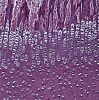

Сверхнадежные HD LCD-камеры, которые сочетают в себе камеру full HD и ЖК-экран retina HD. Благодаря встроенному программному обеспечению DLC-600AF камерами можно управлять с помощью мыши для фотосъемки, видеосъемки и проведения измерений. Оснащенный сенсором Sony COMS и 11,6-дюймовым ЖК-экраном retina HD разработан специально для различных применений в микроскопии. DLC-600 AF имеет функцию автофокусировки и фокусировки в один клик.

Подходят для использования в медицинской диагностике, промышленном производстве и инспекции, лабораторных исследованиях и смежных областях микроскопии для получения изображений, видеосъемки и анализа, а также в следующих областях:

• изображение живых клеток;

• хирургическая микроскопическая визуализация;

• патология;

• цитология;